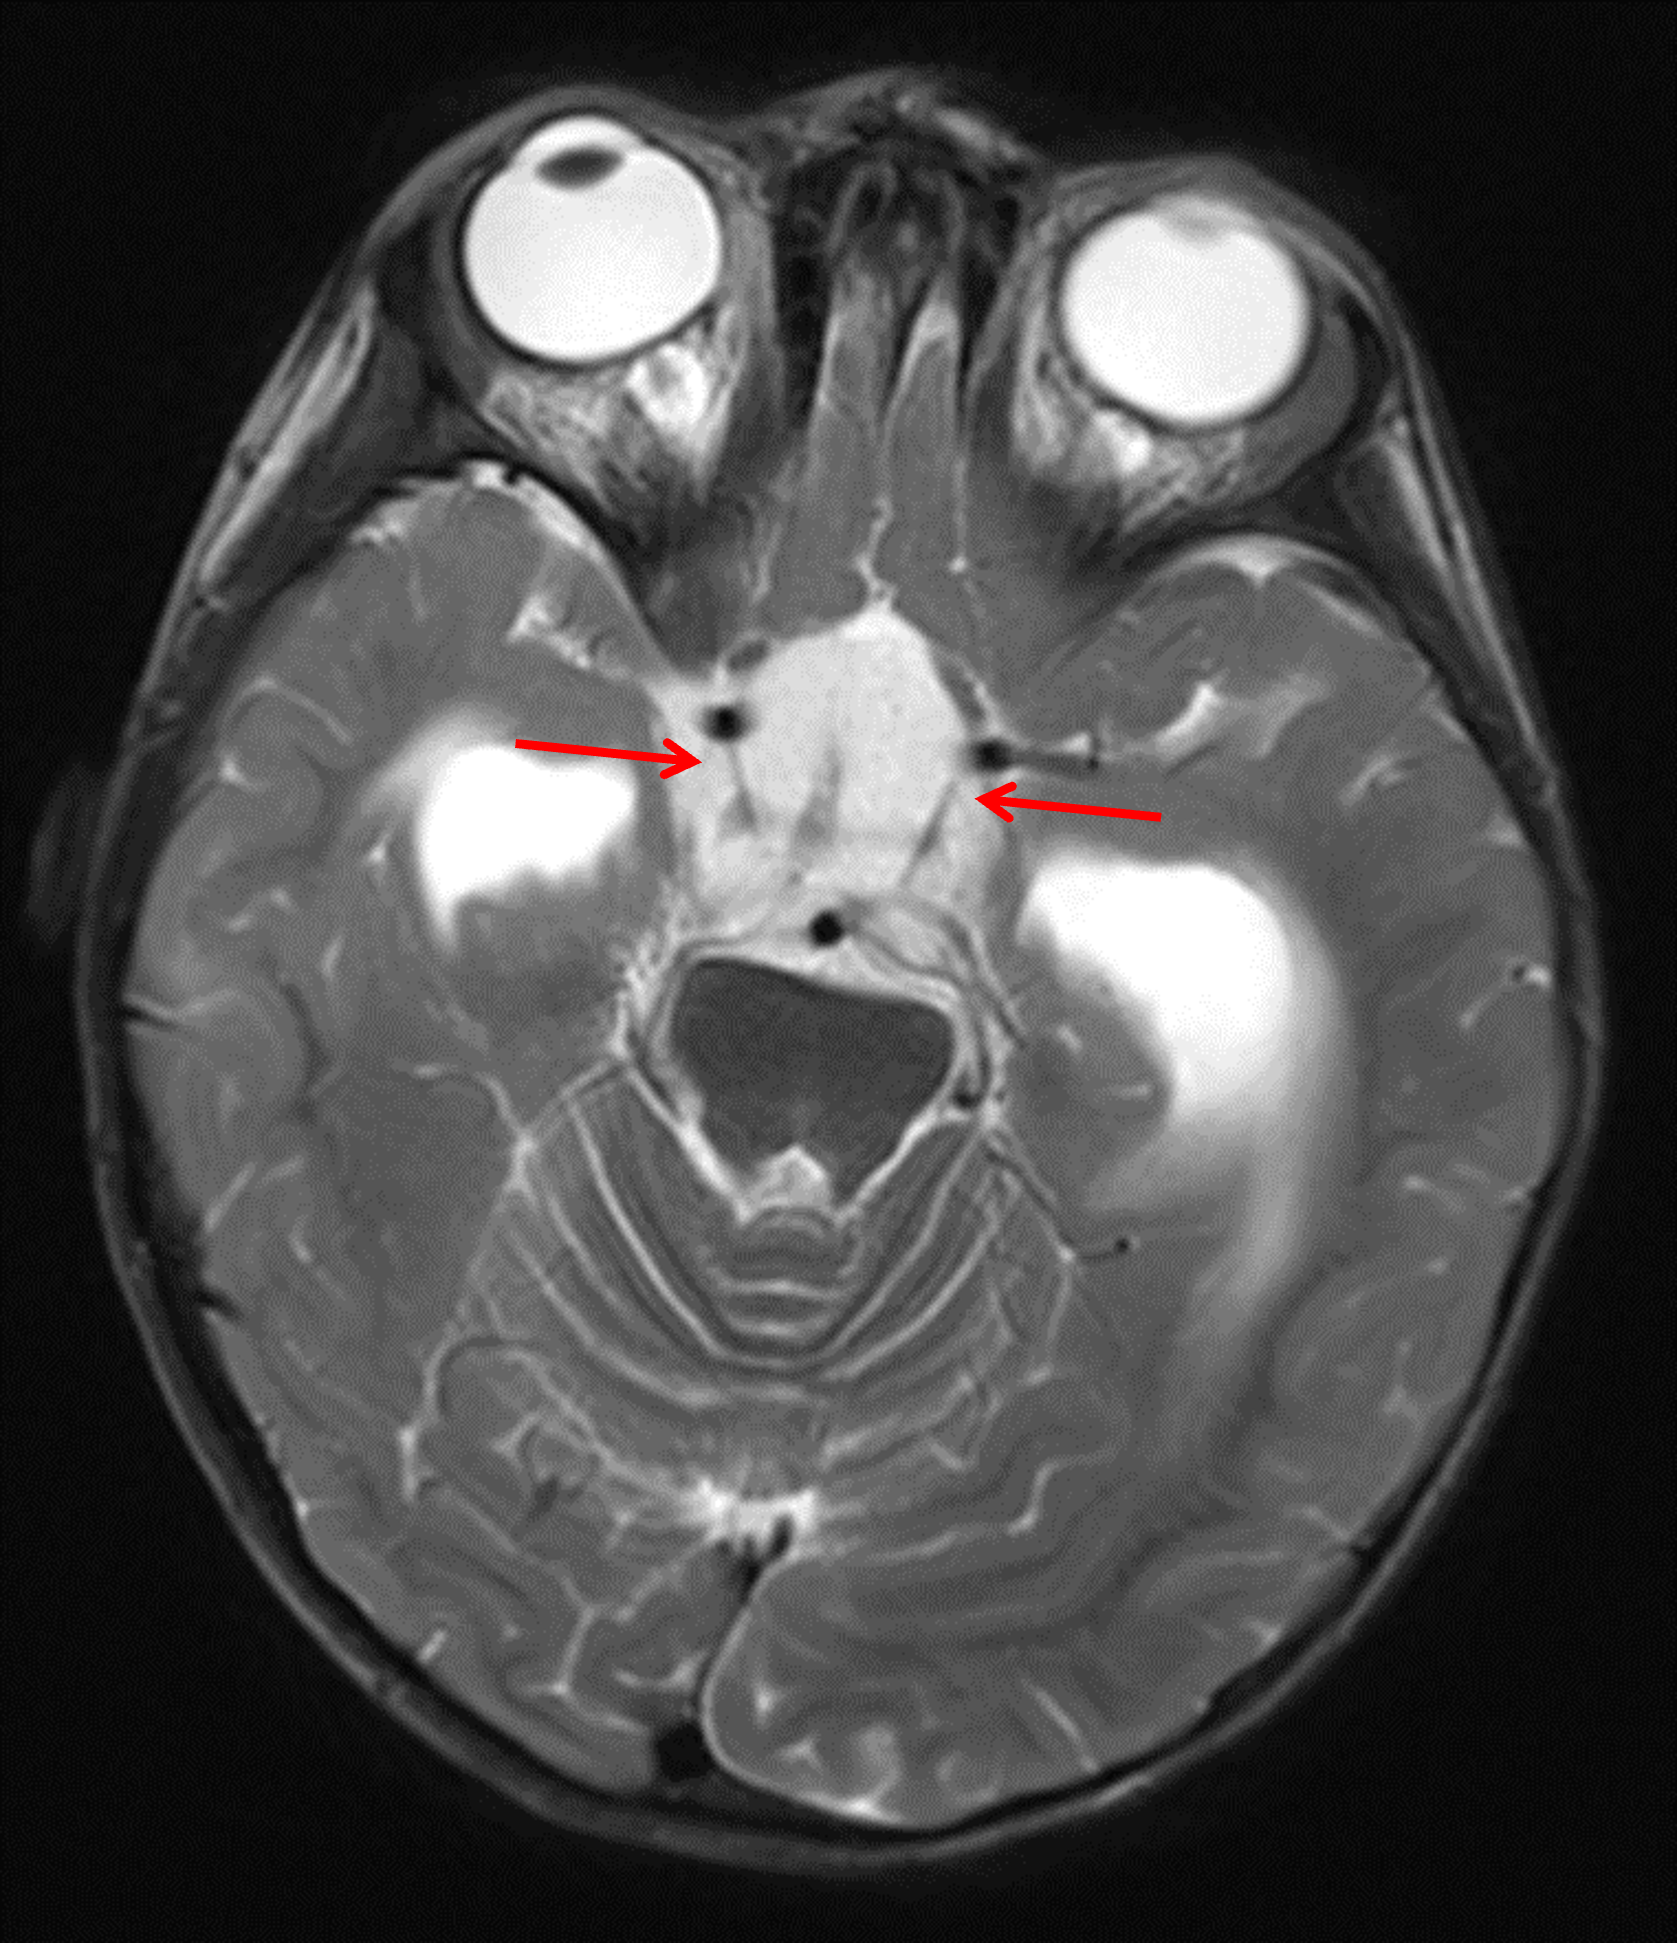

Age: 2

Sex: Female

Indication: Failure to thrive

MRI

Pilomyxoid astrocytoma